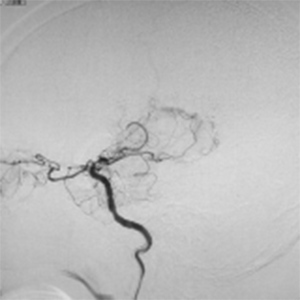

閉塞した脳血管

バイパス術で増加した脳血管